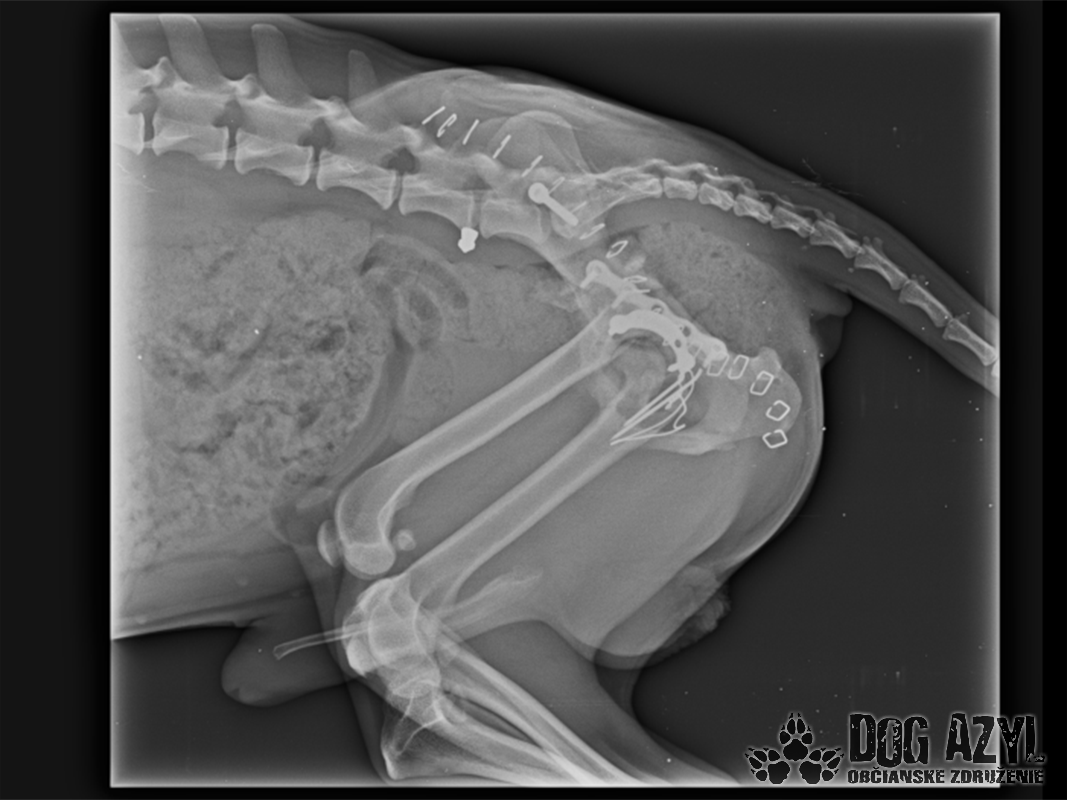

Vianoce nám klopú na dvere a mali by to byť sviatky radosti a pokoja. No u nás nebudú a pre malého Jamesa už vôbec nie. Malého Jamesa sme prijali s mnohonásobnými fraktúrami panvy. Presnejšie, s obojstrannou iliosakrálnou luxáciou/fraktúrou, viacnásobnou fraktúrou panvy, vrátane fraktúry kranialneho acetabula obojstranne. Áno, znie to hrozivo a keď si pozriete snímky z RTG, bude to ešte hrozivejšie (ďalšie snímky ešte doplníme).

Čakali ho teda štyri, veľmi náročné ortopedické operácie, takže sa musel trocha posilniť. Do starostlivosti si ho vzala MVDr. Panyi Terzieva a 17.11. mohol absolvovať prvú operáciu. V "prvom kole" krpec zvládal anestézu tak dobre, že sa rovno mohli spojiť dve operácie a tak sa celá ľavá strana dala do poriadku. Zostal samozrejme naďalej hospitalizovaný. Ďalší zákrok sa naplánoval na 20.11. a našťastie opäť všetko prebehlo hladko, a zoperovala sa celá pravá strana(nechceme sa dlho rozpisovať, prikladáme lekársku správu). James bol prepustený 24.11. ako chodiaci pacient a bez problémov ovládal aj vylučovanie! Je to priam zázrak, za ktorý opäť vďačíme MVDr. Vatolíkovi a jeho teamu.